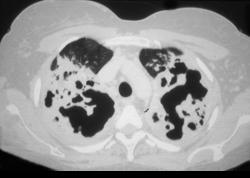

问题 一养鸽女,48岁,发热,咳嗽,咳脓痰带血半月余,请结合CT检查选出最可能的诊断 ( )

选项 A、间质性肺炎 B、支气管扩张 C、肺曲菌病 D、肺癌 E、原发性肺结核

答案 C